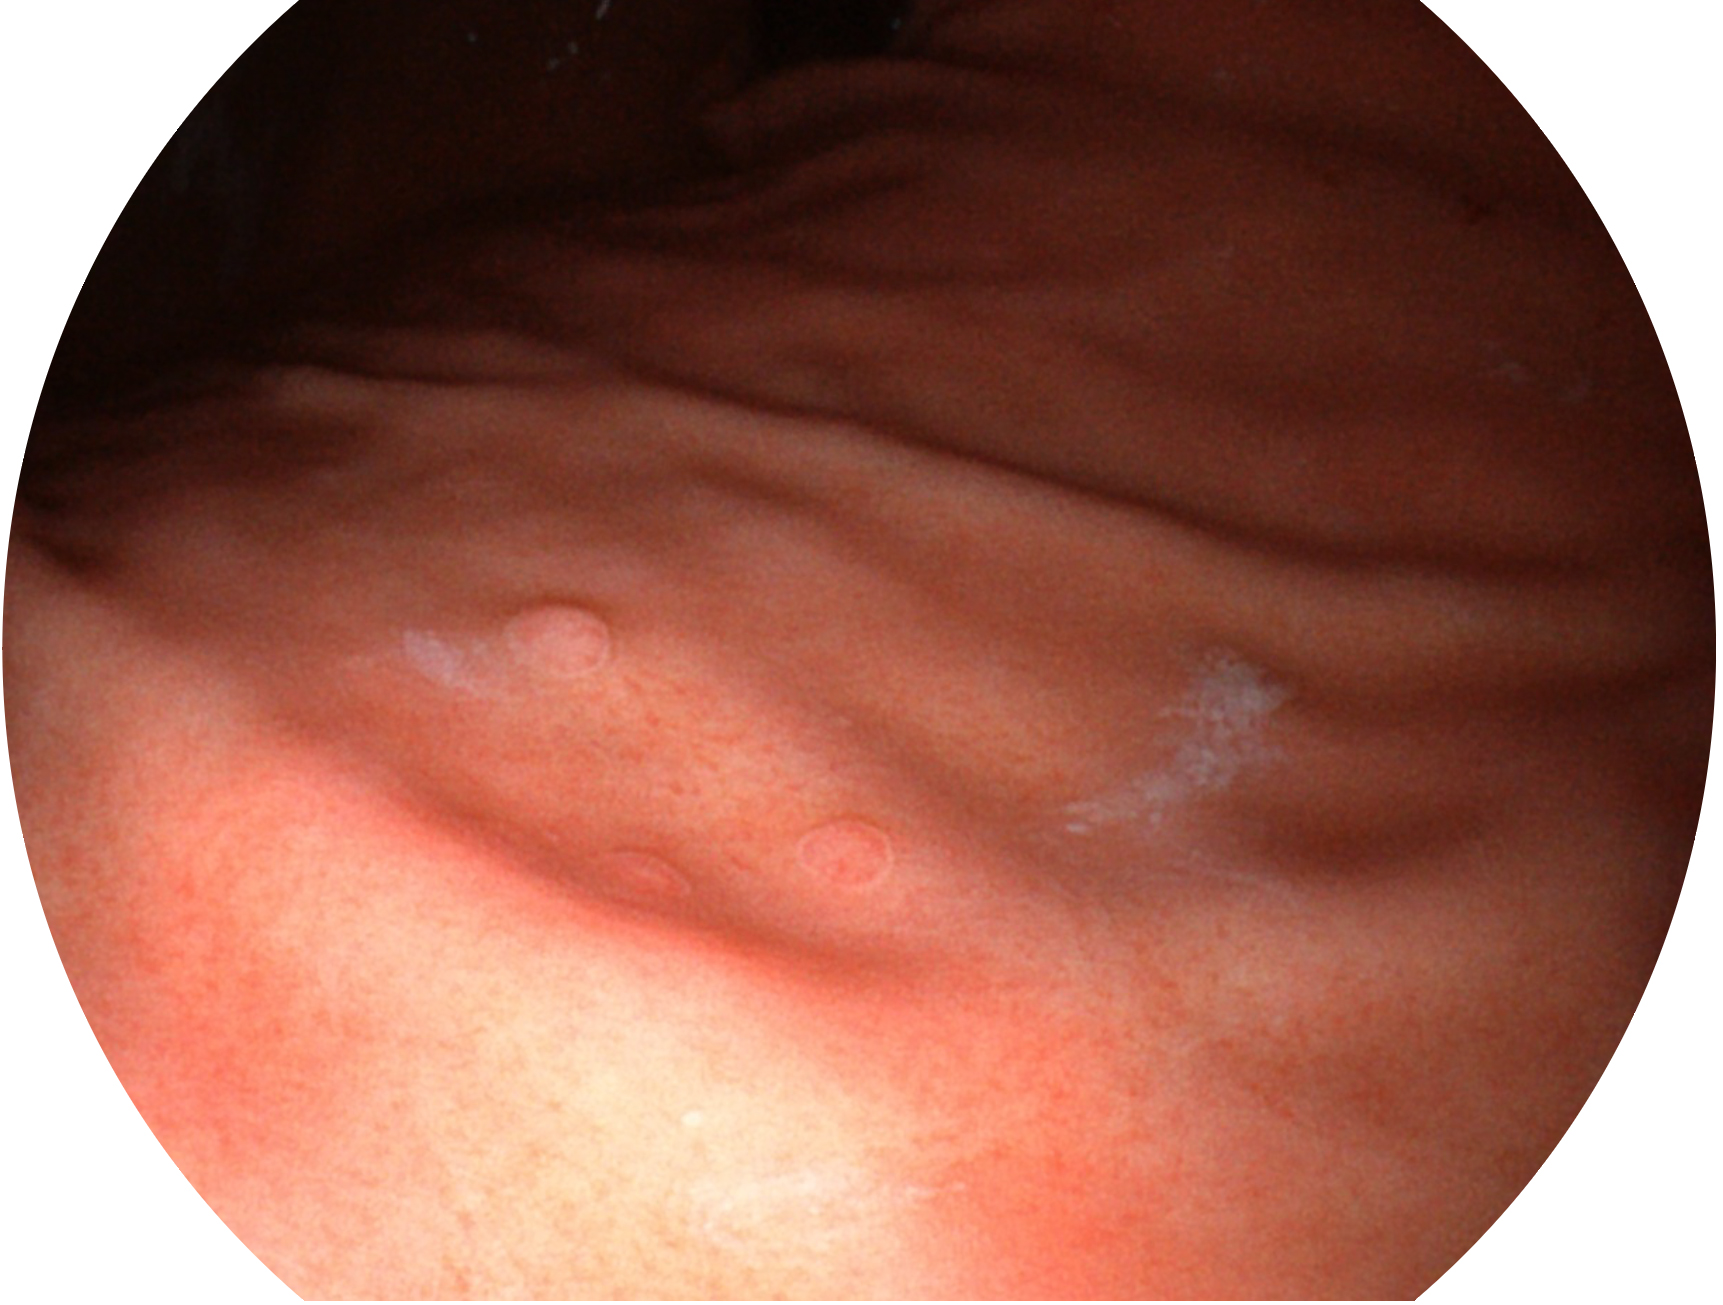

SFI技术是结合特定光谱照明与数字光谱滤波,实现高亮度特殊光成像。染色模式下,不改变粘液、食物残渣、粪液等基本颜色,在保持与白光照明相似的图像色调的同时突显了图像颜色的红白对比度,且在远距离观察的情况下具备与普通白光模式相同的图像亮度,有助于消化道疾病的大范围扫查和早癌筛查。

• 白光图像 SFI图像